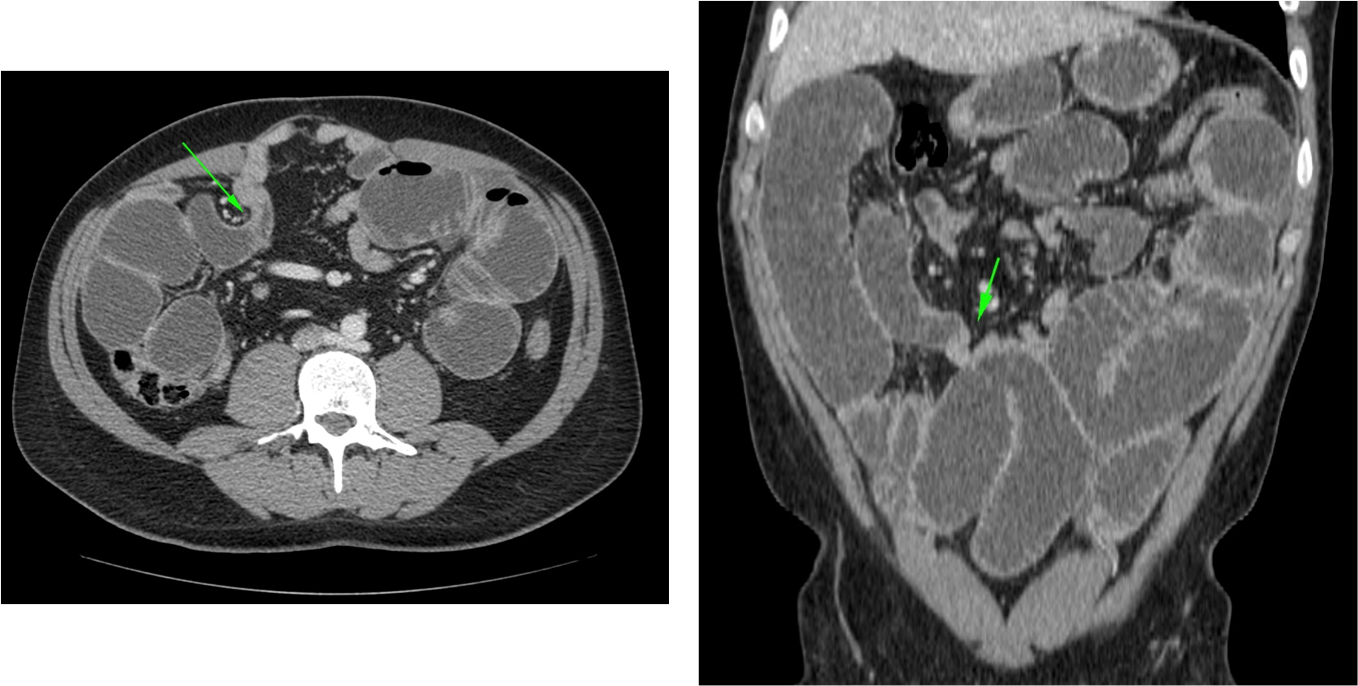

INVAGINACIÓN INTESTINAL.

La invaginación intestinal es la introducción telescópica de un segmento de intestino junto con su mesenterio, dentro de la luz de otro segmento contigüo más distal. En una invaginación, la porción de intestino que se invagina, arrastra su meso acompañante, lo cual origina una compresión del retorno venoso. Si esto no se soluciona a tiempo, se produce edema, hemorragia, obstrucción y gangrena.

El diagnóstico actual de la se realiza mediante TC abdominal:

- El hallazgo patognomónico es el signo de la escarapela o diana identificable en la TC o ecografía.

- Podemos ver la imagen de “Intestino dentro de intestino” gracias a las reconstrucciones multiplanares.

Invaginación de Intestino Grueso

- Suele deberse a una lesión subyacente, sobre todo procesos malignos primarios.

- Resto son causas benignas (lipomas, polipos adenomatosos) o idiopáticas.

- Díficil determinar la causa subyacente, excepto en el lipoma (atenuación grasa) o si existe enfermedad metastásica abdominal conocida.

- El lipoma constituye la causa benigna más frecuente de invaginación colo-cólica y el adenocarcinoma de colon la causa maligna más frecuente.